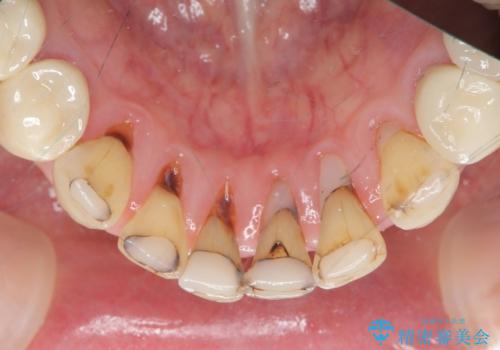

シェーグレン症候群で多発した虫歯 前歯のセラミック治療

唾液分泌が減少すると、虫歯になりやすく、小さな虫歯にコンポジットレジンを充填を繰り返した結果 写真のような継ぎ接ぎだらけの歯になってしまいます。

充填されていたコンポジットレジン・小さな虫歯を丁寧に全て取り除いたのち、歯全体を覆い虫歯の再発予防を期待できるセラミッククラウンで補綴を行います。

コンポジットレジン修復は小さな虫歯を除去したのちの充填には向きますが、充填箇所が複数になってくると審美障害や虫歯の再発リスクが高まります。